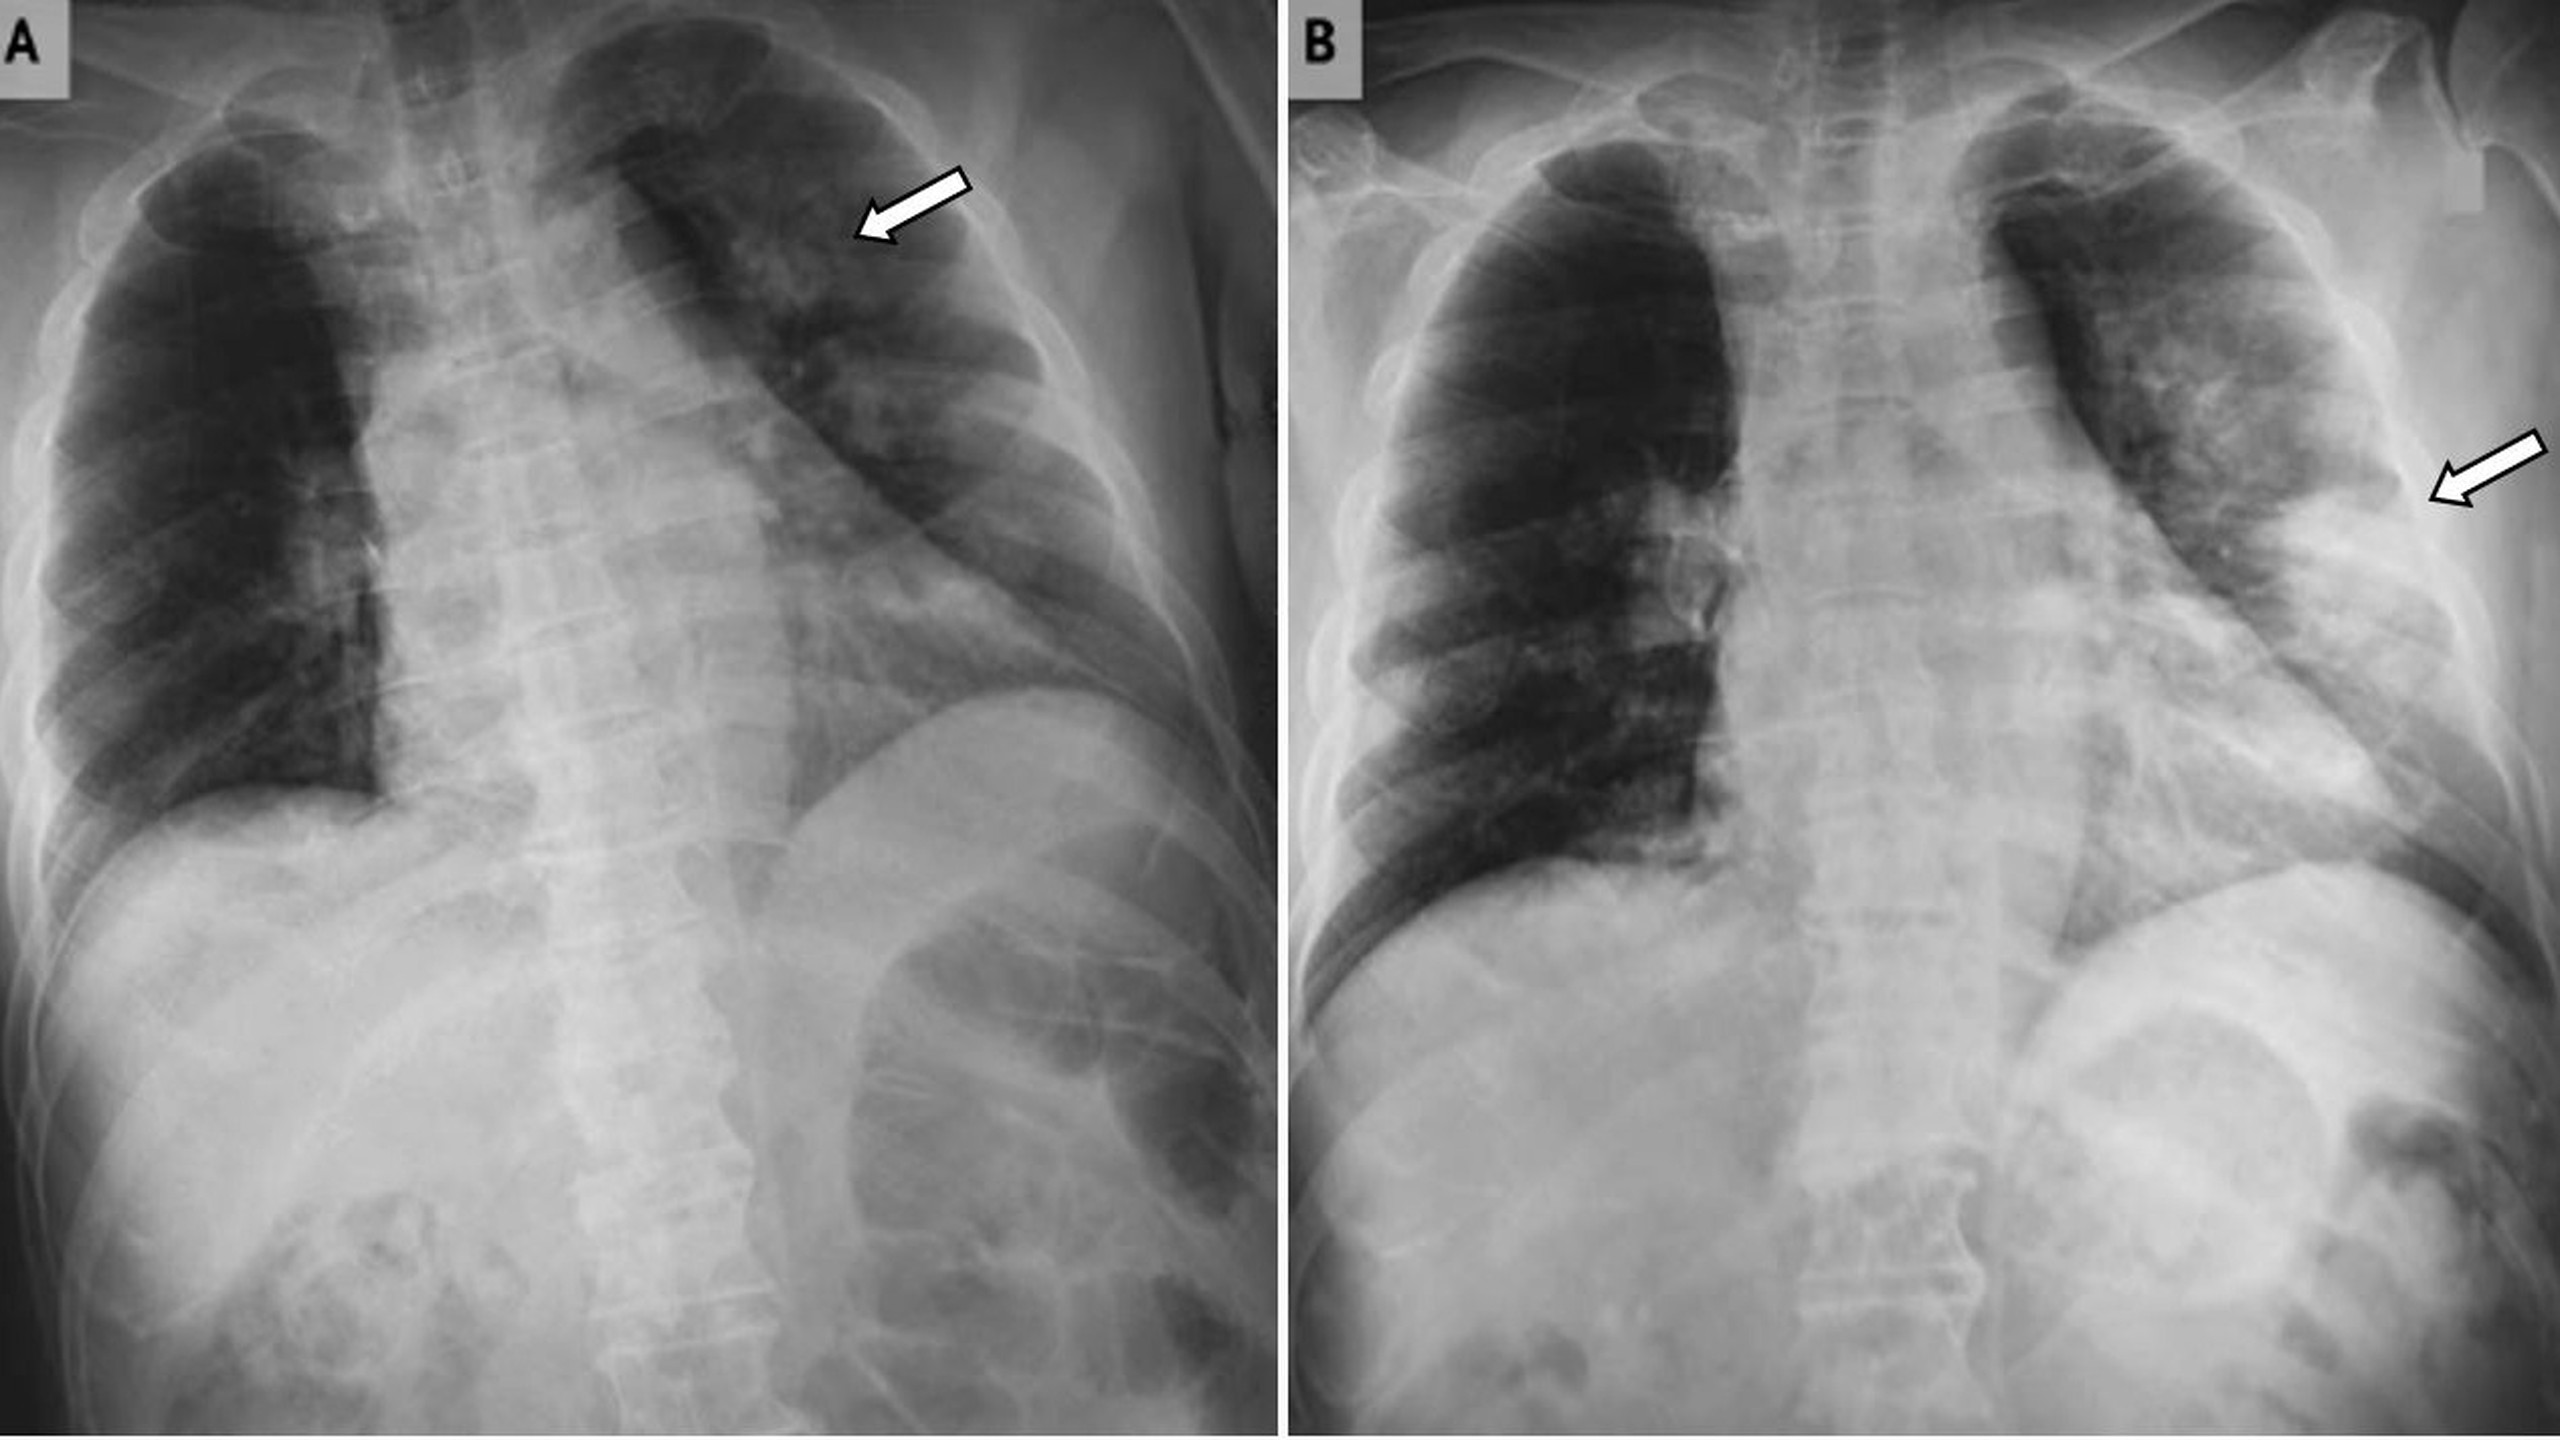

Nhồi máu phổi là do sự tắc nghẽn ở mạch máu phổi. Điều này sau đó dẫn đến thiếu máu cục bộ và có thể xuất huyết hoặc hoại tử mô của mô phổi. Nhồi máu phổi là bệnh lý tuy hiếm gặp nhưng rất nguy hiểm, cần chẩn đoán sớm và điều trị kịp thời để không ảnh hưởng đến tính mạng.

Nhồi máu phổi là do sự tắc nghẽn ở mạch máu phổi. Điều này sau đó dẫn đến thiếu máu cục bộ và có thể xuất huyết hoặc hoại tử mô phổi. Trong hầu hết các trường hợp, nguyên nhân dẫn đến nhồi máu phổi thường là do thuyên tắc phổi.

Tùy thuộc vào kích thước và vị trí, triệu chứng sẽ khác nhau ở mỗi người, từ nhẹ đến rất nghiêm trọng. Tuy nhiên, bất kể triệu chứng của nó là gì, khi nhồi máu phổi xảy ra, điều đó luôn có nghĩa là có một vấn đề y tế nghiêm trọng và cần được đánh giá và điều trị tích cực.